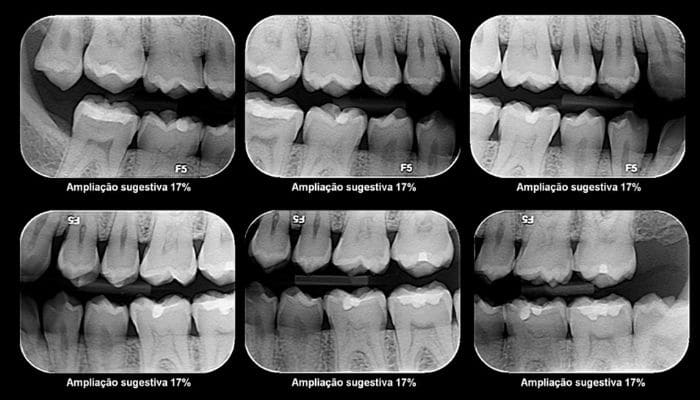

Algumas imagens de como podemos ajudá-lo a alcançar o sorriso dos seus sonhos: